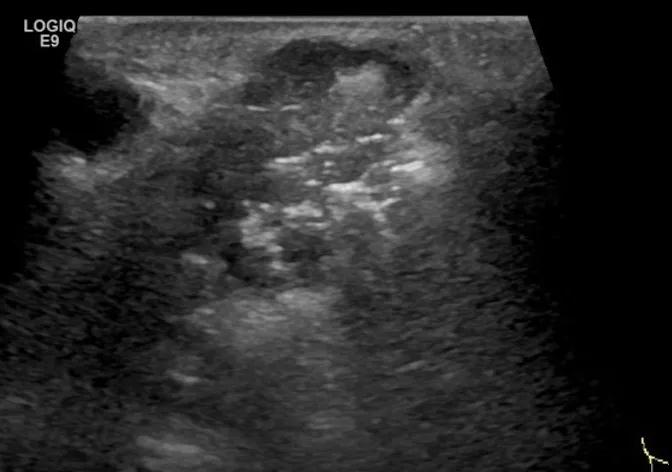

随后,徐栋教授进一步分享了五个临床实战病例,带来了更直观的热消融治疗经验。第一个病例是62岁肺癌患者,术后1年余发现双侧锁骨上淋巴结复发,侵犯神经,存在静脉回流、淋巴回流障碍,肿胀、疼痛非常明显。影像显示患者淋巴结边界不清、形态不规则,存在浸润,血流强化增强。由于患者在系统治疗后进展,且主要目的缓解症状、减瘤。局麻下行热消融术,从后向前逐层消融,热消融之后超声造影即刻评估显示完全充盈缺损,完全覆盖病灶。

(病例1图例)